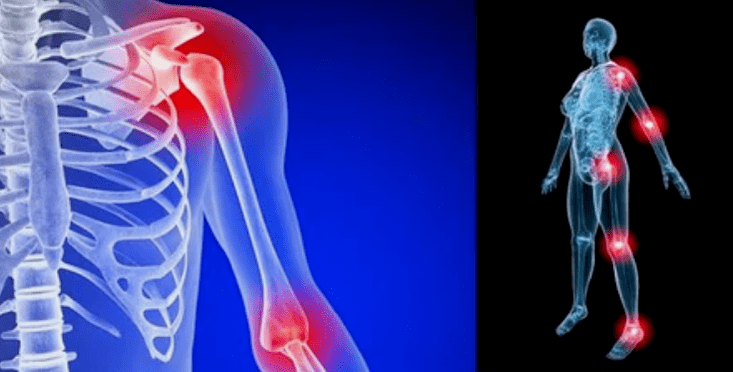

The manifestations of the disease vary slightly depending on the location, more often the signs affect the knees, shoulders and hip joints due to the high load.

- pain.They have a low severity at the initial stage, and the deterioration of the condition of the sensation intensifies.Initially, the joints only hurt after waking up, after a slightly warm, the sensations disappeared.Over time, the pain occurs at night, they significantly disturb during and after long walking, running, etc.In the last stage, the pain syndrome pursues a person all the time;

- Swelling with redness.It is located near the diseased joint, this indicates an inflammatory process and progression of the disease.The doctor understands that the synovial sheath is affected, this provokes fluid accumulation and increased pain;